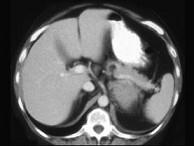

问题 女,47岁,满月脸、向心性肥胖伴高血压1个月,请结合所提供图像,作出诊断 ( )

选项 A、左肾上腺嗜铬细胞瘤 B、左肾上腺增生 C、左肾上腺腺癌 D、左肾上腺转移瘤 E、左肾上腺腺瘤

答案 C